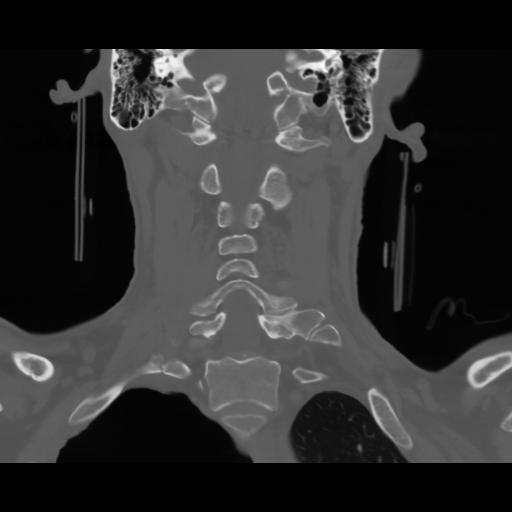

13 P.BLANDAS,,Coronal,2.000,P.BLANDAS,Coronal,